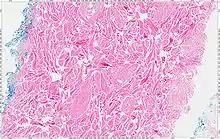

The tumors are unencapsulated and poorly circumscribed, showing a firm, white cut surface. Most tumors are about 3.5 cm, but can be up to 8 cm.[1] By microscopic examination, there are haphazardly arranged thick collagen fibers, with a low cellularity and no pleomorphism. There are usually entrapped fat cells, skeletal muscle, and peripheral nerves. The may be perineural fibrosis. The elastic fibers may be altered, which is why an elastofibroma is considered in the differential diagnosis.[1]